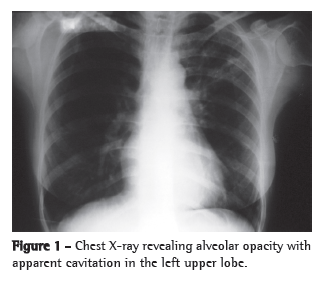

The patient stated that she was not a smoker or an alcoholic. She reported that she had tested negative on a tuberculin skin test (TST) conducted before the initiation of adalimumab treatment, and that, according to the rheumatologist who treated her, a chest X-ray performed at the time was normal. After the use of azithromycin (three and half months prior), she also received an additional infusion of adalimumab. Physical examination revealed mild pallor and no palpable lymph node enlargement. There were fine rales in the upper third of the left hemithorax and coarse rales in the middle third of the right hemithorax, as well as scattered rhonchi. Her hands and feet had joint deformities. A chest X-ray revealed alveolar opacities in the left upper lobe, left lower lobe and middle lobe, as well as images suggestive of bronchogenic dissemination (Figure 2). A CT scan of the chest revealed tree-in-bud centrilobular opacities (Figure 3).